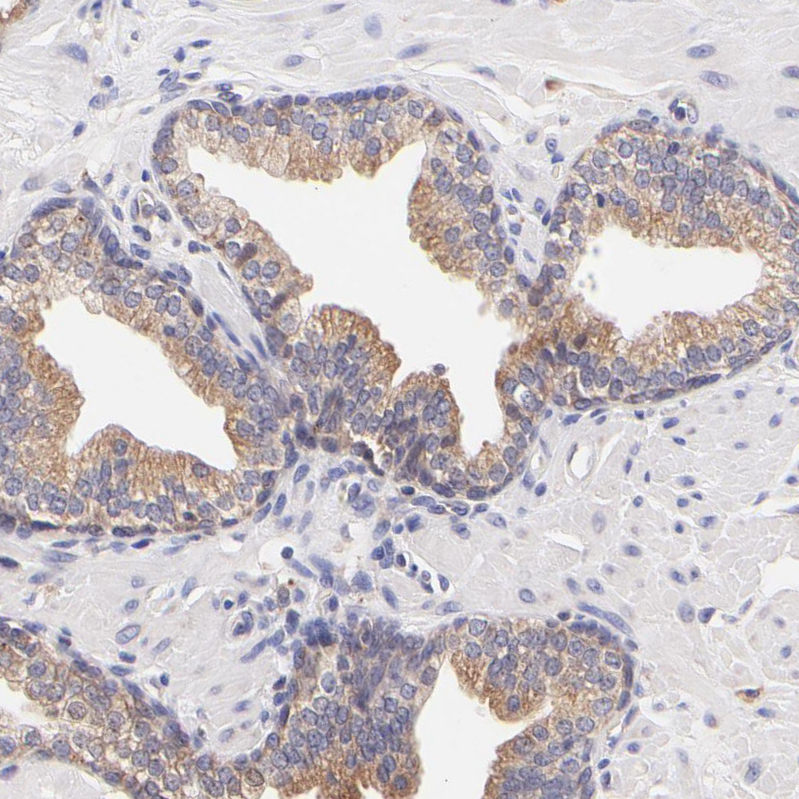

Immunohistochemical staining of human Fallopian tube shows moderate cytoplasmic positivity in glandular cells.